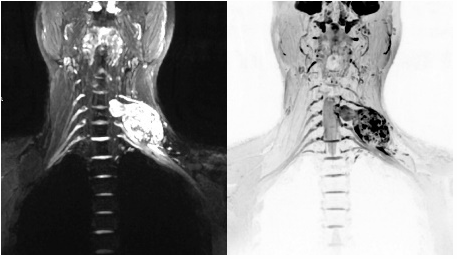

臂丛神经是支配上肢运动的主要神经,臂丛神经损伤通常是因为外伤和产伤等因素导致的,是一种比较严重的神经损伤,对于患者的生活质量和身心健康会造成十分严重的危害,也是周围神经损伤中最为复杂的一种,且诊断较为困难。以往临床诊断主要根据病史、症状、体征, 依靠肌电图、诱发电位等电生理检查, 缺少臂丛神经解剖结构及病变的直观显示。而对于臂丛神经损伤的诊断与治疗,首先要准确的进行定位、定性诊断,才能有效的进行治疗、恢复,从而达到一个最好的疗效。

病例

术前检查